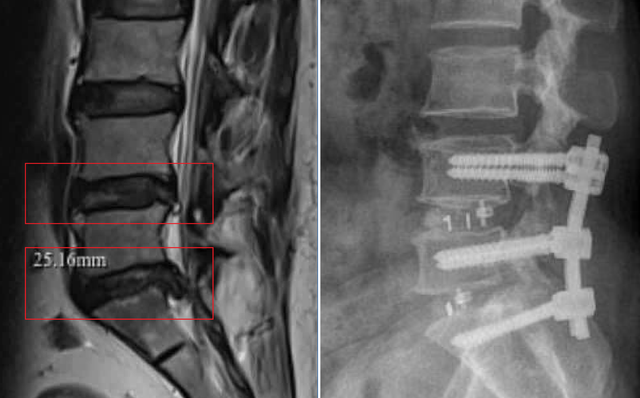

Cột sống của người bệnh trước và sau phẫu thuật

Kết quả chẩn đoán MRI cho thấy, bà N. bị thoái hóa cột sống kèm thoát vị đĩa đệm đa tầng (L4–L5; L5–S1) gây chèn ép rễ thần kinh cột sống – nguyên nhân khiến bà đau lưng nhiều năm và nguy cơ liệt chi nếu không được điều trị kịp thời.

Sau khi đánh giá toàn diện, ê-kíp phẫu thuật đã lựa chọn phương pháp TLIF nhằm giải phóng rễ thần kinh bị chèn ép, đồng thời tái tạo sự vững chắc cho cột sống.

Với trường hợp của bà N., tình trạng thoái hóa cột sống kèm thoát vị nặng buộc ê-kíp phải lựa chọn tiếp cận từ phía sau – nhằm xác định chính xác vị trí tổn thương, giải phóng rễ thần kinh đa tầng và đặt vít chân cung tái tạo cột sống vốn đã suy yếu.